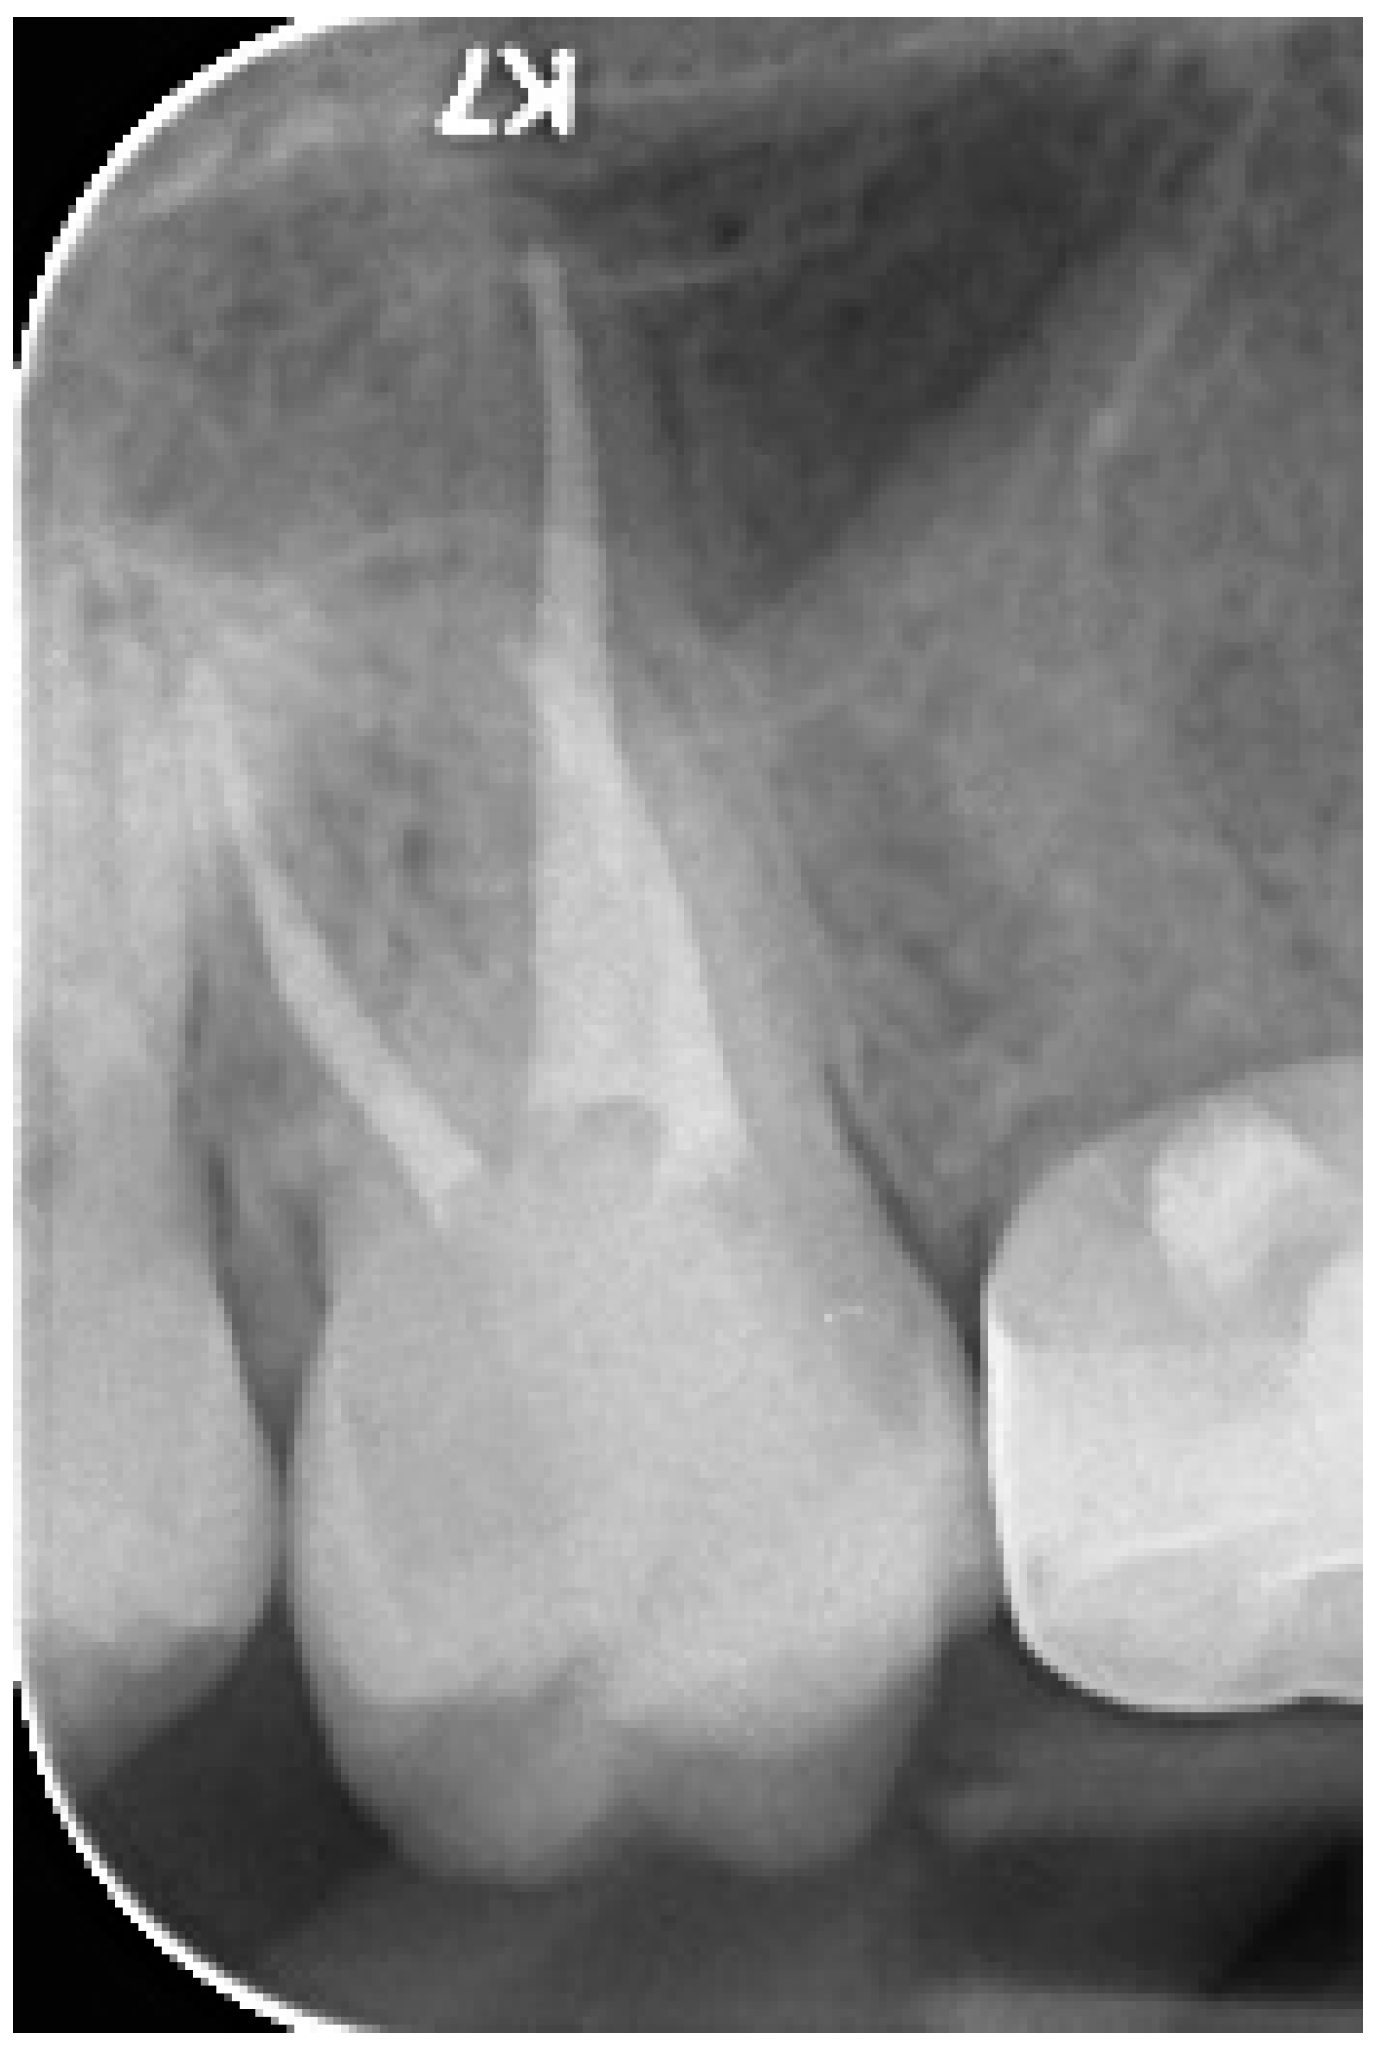

2.2. Clinical Case